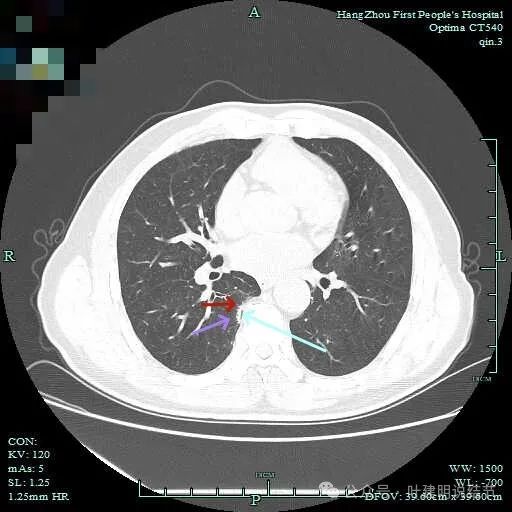

病灶实性伴细毛刺,与脊柱间有间隙在。

病仍明显,从上到下,觉得应该是成片的。

表面不平毛刺,实性密度为主。

微小血管有,但无异常增粗。

病灶实性,边缘不光滑。